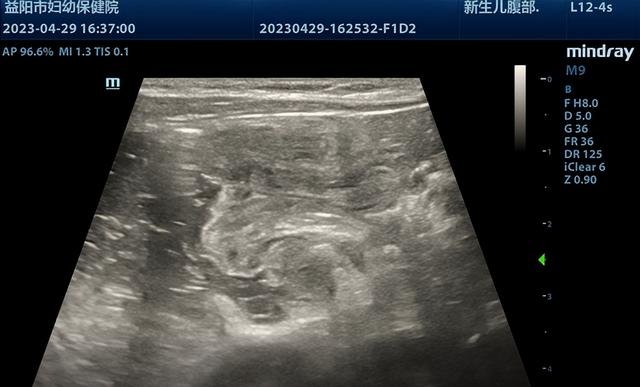

近日,一名仅11个月的小宝宝因呕吐1天来益阳市妇幼保健院就诊,经超声检查可见肠套叠特异征象“套筒征”及“同心圆征”,套入部分肠管长度较长,约60mm,诊断为回结型肠套叠。

超声实时监视下,见生理盐水缓缓充盈结肠至回肠套叠部位。由于患儿套入肠管较长,经操作医生辅以手法按摩,套入回盲部肠管缓慢退出,回盲瓣成功开放,小肠进液,复位成功。整个过程不到半小时。